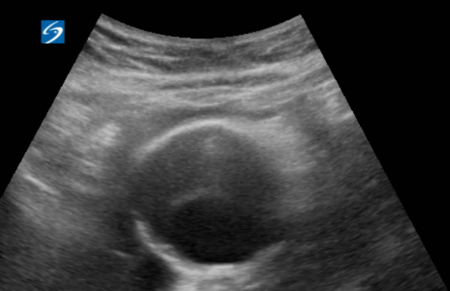

A 75-year-old female with a significant past medical history of hypothyroidism, and allergies to levothyroxine, presented to the emergency department with pain around her shoulder blades and shortness of breath. The patient described the pain as sudden in onset and denied any trauma to the back, heavy lifting, or physical activity. She denied any recent sickness, fevers, chills, chest pain, nausea, or diarrhea. On physical exam the patient appeared in acute distress and uncomfortable due to severe pain but otherwise her physical exam was unremarkable. Patients' vitals demonstrated hypertension, with initial blood pressure of 194/109. POCUS showed large aortic aneurysm (Figure 1). Computed tomographic angiography (CTA) of the chest demonstrated diffuse aortic wall abnormalities with extensive mural thrombus and irregular wall appearance (Figure 2). Areas of high attenuation within the aortic wall suggested the presence of blood products, indicating an acute on chronic process with mural ulceration and likely penetrating atherosclerotic aortic ulcers with blood dissecting into the aortic wall. Additionally, imaging revealed a large infrarenal abdominal aortic aneurysm measuring 5 cm, without evidence of rupture or extravasation. Patient was started on an esmolol drip, admitted to the ICU with consultation by Cardiothoracic surgery and Vascular surgery.

Point-of-care ultrasound demonstrating an infrarenal abdominal aortic aneurysm

Figure 1. Point-of-care ultrasound demonstrating an infrarenal abdominal aortic aneurysm.